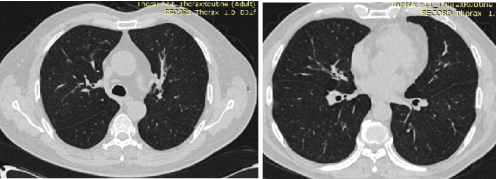

2024年ISHAM关于ABPA的建议如下[7]:血清总IgE≥500 IU/ml(LoC:71.8%)和血嗜酸性粒细胞计数≥500 cells/μl用于诊断ABPA(LoC:73.0%);不建议使用血清半乳甘露聚糖诊断ABPA(LoC:92.3%);建议评估ABPA时推荐进行痰真菌培养(LoC:100%),这可能有助于确定种类或指导治疗(LoC:61.5%);建议在基线时进行胸部薄层CT检查,以确定可疑ABPA患者的支气管扩张、黏液堵塞、高密度黏液栓和其他异常(LoC:92.3%);建议使用胸片评估ABPA的治疗效果(LoC:62.3%)。不常规推荐支气管镜检查用于诊断ABPA(LoC:86.1%)。